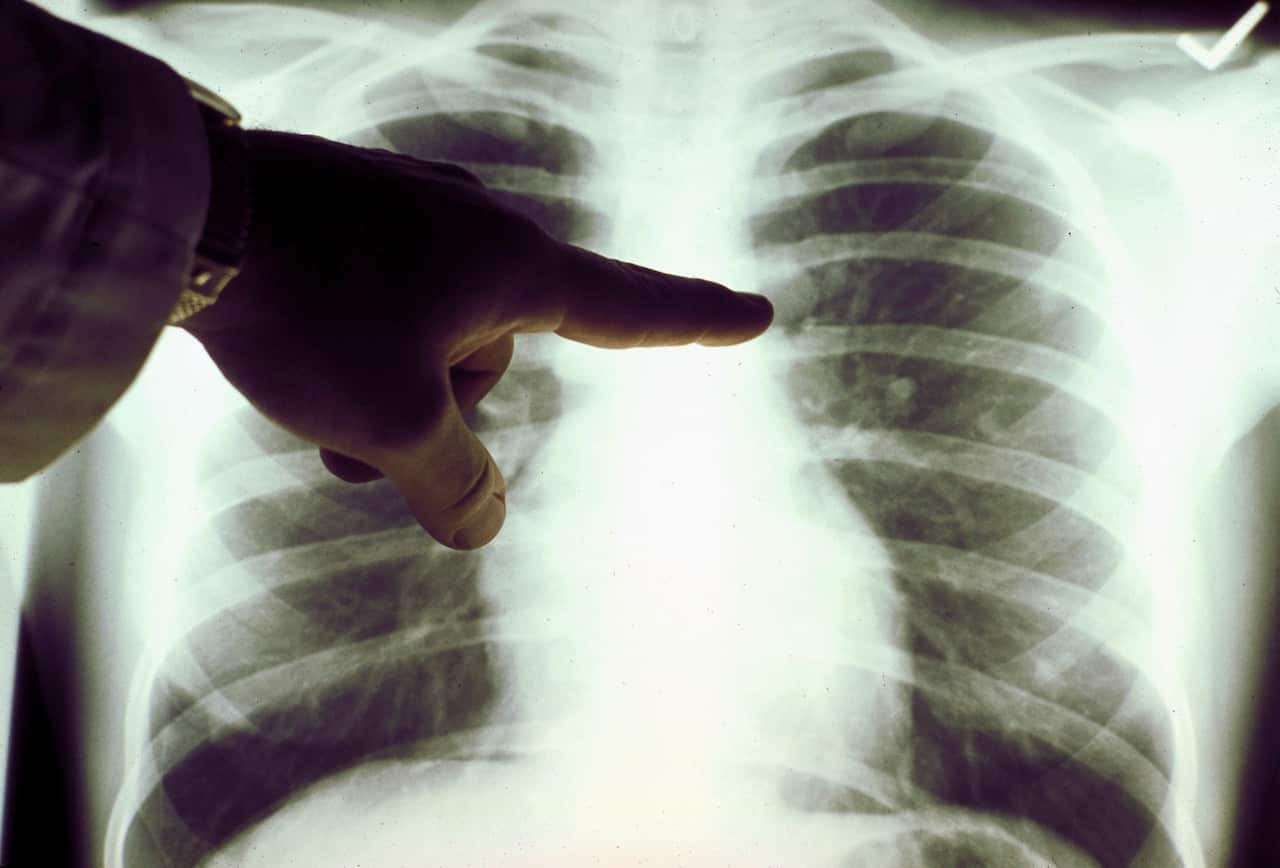

矽肺病是这一人群中常见的、不可逆的职业病。它会导致肺部纤维化与疤痕形成、造成呼吸困难与结节。很多时候,病情会逐渐加重,患者会死亡。有关矽肺病的详细描述请参见SafeWork Australia网页。